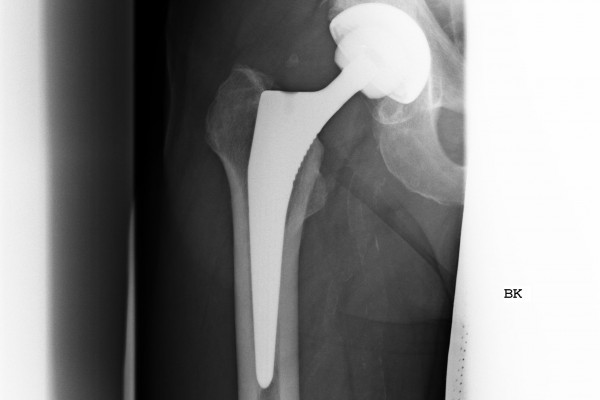

Wechsel eines Hüftgelenkschaftes

Im Falle einer Schaftlockerung mit wenig Knochendefekt ist es möglich das vorhandene Implantat in ein größeres Implantat zu wechseln.

Bei größeren Knochendefekten wird der Austausch mit Hilfe eines modular aufgebauten Schaftrevisionssystems durchgeführt.

Hierbei können auch längerstreckige Defekte des Knochens und Knochenbrüche in stabile Situationen geführt werden.